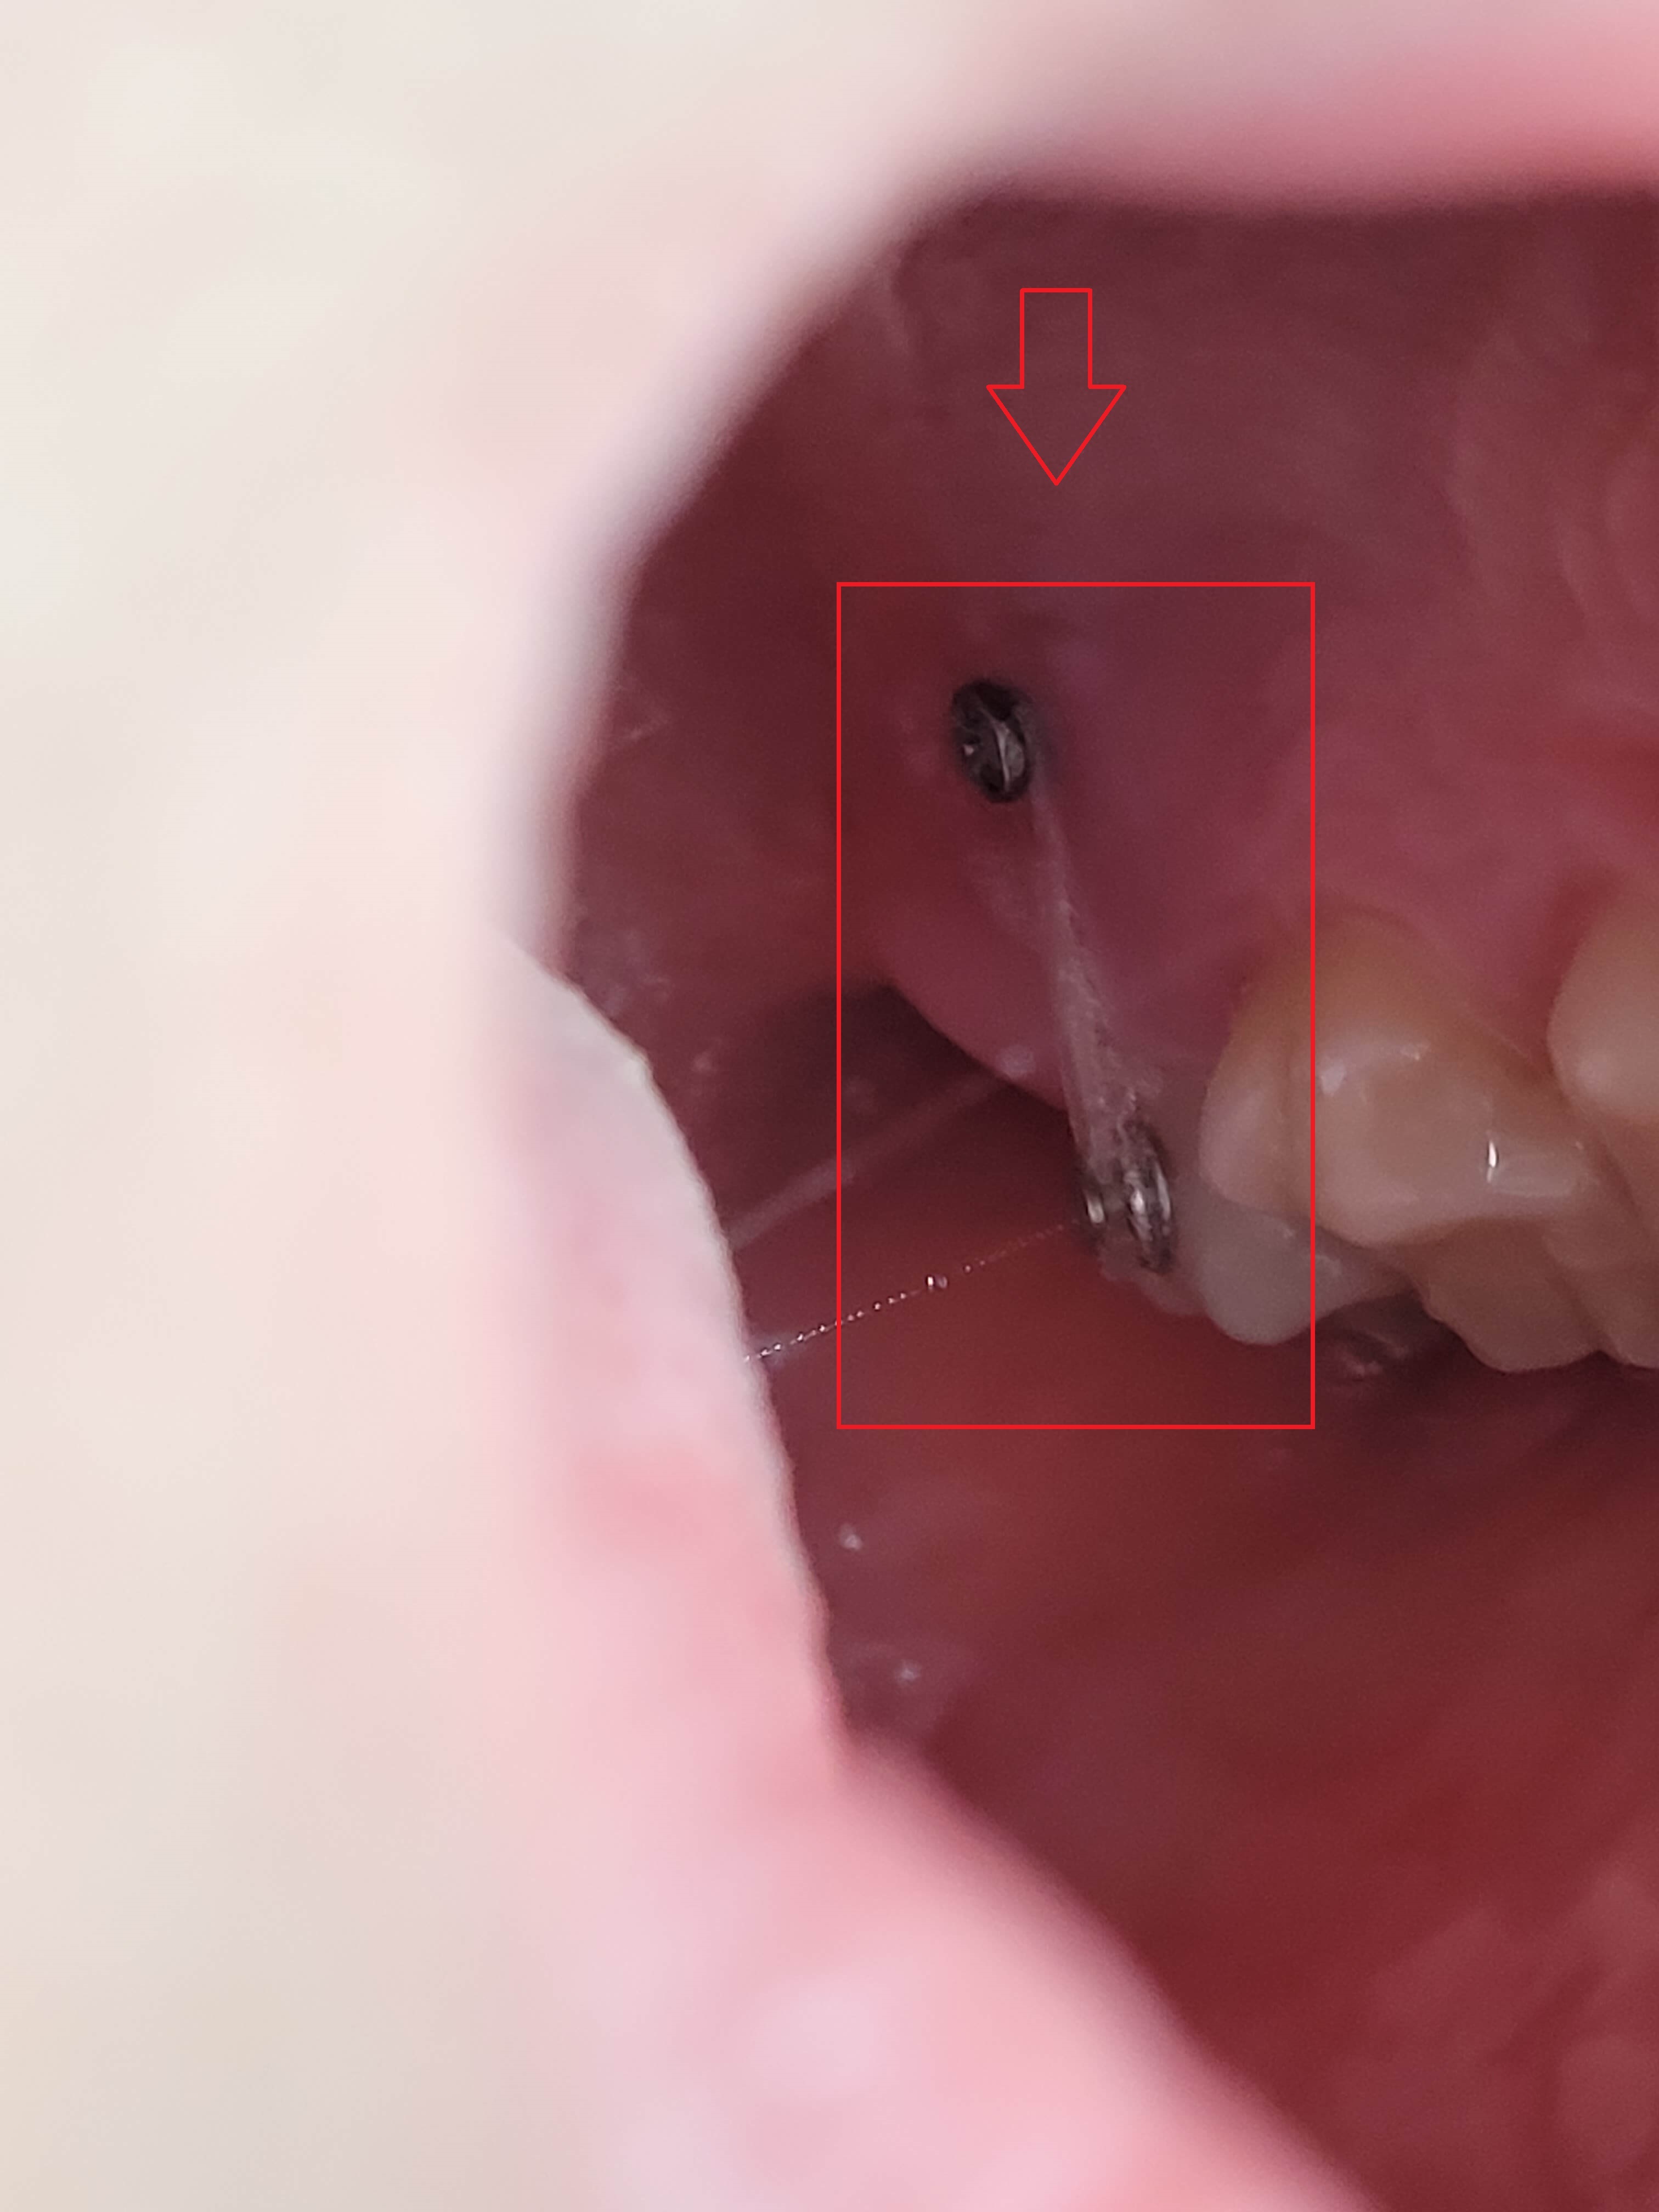

▼ 아래 어금니 블라켓으로 고정후 힘을 주어 당기고 있는 모습

▼ 윗 어금니는 스크루를 박고 체인으로 묶어서 한 단계씩 줄여나가면서 이동시킴.

위, 아래 어금니가 모두 그렇는데 아래 어금니는 브라켓 설치로 힘을 주어 잡아당기고 있고 윗 어금니는 스크류를 박고 고무줄(체인)로 잡아당기고 있습니다.